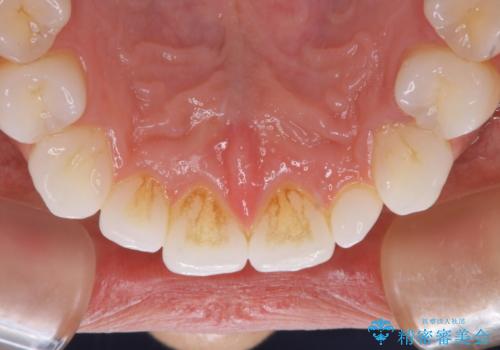

治療症例の内容

- 20代女性

- 1日

- しばらく歯科でのクリーニングをしていないため、きれいにしたいとのことでした。

PMTC30分コースを行いました。

プラークが放置されると、そこで病原菌が繁殖し始めます。そうなるとバイオフィルム(歯面に強固に付着したばい菌の膜)になり、歯肉に炎症が生じ歯周病の引き金となります。

プラークやバイオフィルムといった細菌などを放置すると歯石となります。歯石になってしまうと歯磨きでは取り除くことができないため、歯科医院にて専門的な機械や材料を使用してクリーニングを受ける必要があります。